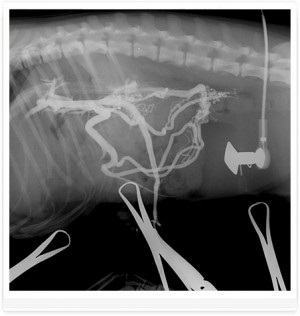

Foto 3. shunts portocaval - venei porte drenaj în vena cava caudală

Foto 4. shunts portocaval - venei porte drenaj în vena cava caudală

Foto 5. Un compus din vena portă și vena cava caudală cu vena nepereche in vena cava segmentul prerenal

Diagnosticul EXEMPLU și tratamentul shunt. Câine rasa Yorkshire Terrier